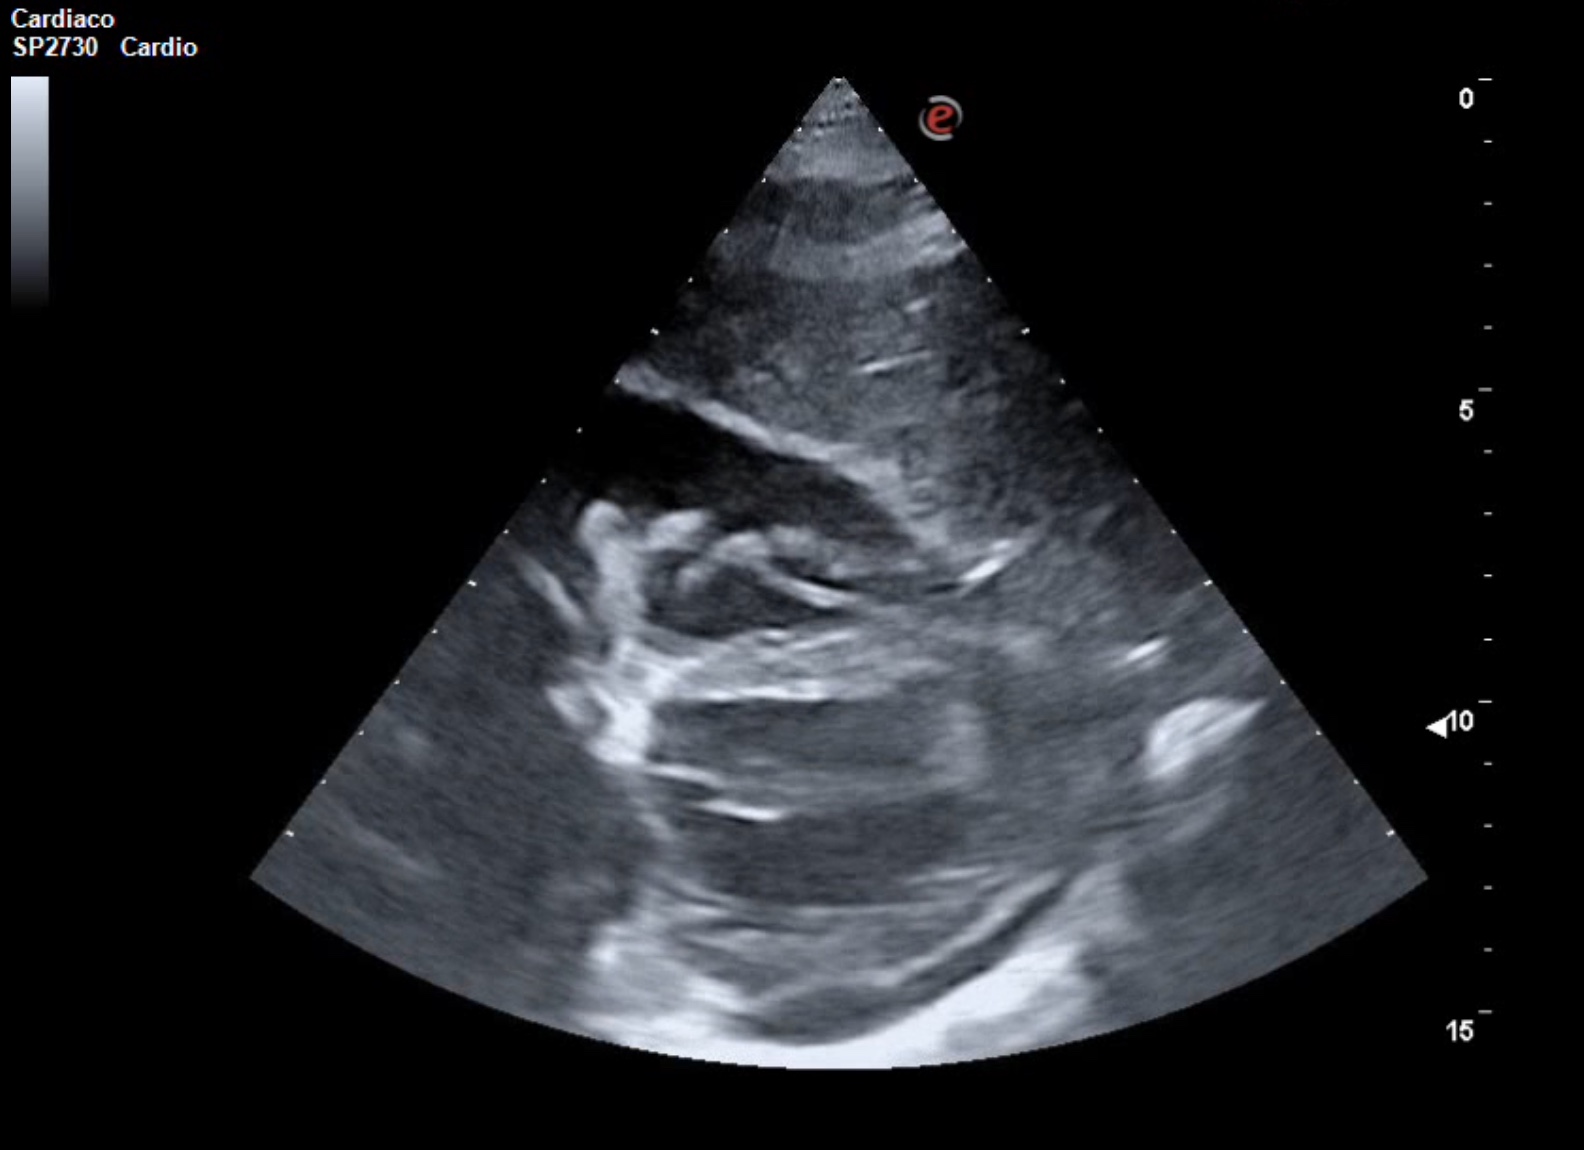

La ecocardioscopia mostró ventrículo izquierdo no dilatado con función sistólica conservada, sin hipertrofia del septo interventricular ni valvulopatías. Aurículas izquierda y cavidades derechas de tamaño normal. TAPSE normal. Se evidenció un derrame pericárdico moderado sin signos de taponamiento cardíaco. Calibre de vena cava inferior normal con colapsabilidad mayor del 50%. Hallazgo de derrame pleural derecho moderado.

La ecografía clínica desempeñó un papel fundamental en la evaluación inicial del paciente, permitiendo una detección rápida y precisa de hallazgos que guiaron la toma de decisiones clínicas. La ecocardioscopia realizada reveló un derrame pericárdico moderado, sin signos de taponamiento cardíaco y un derrame pleural derecho significativo. Estos hallazgos fueron esenciales para descartar la presencia de un cuadro obstructivo que pudiera haber requerido una intervención inmediata. Además, la ecografía permitió valorar el estado hemodinámico de la paciente de forma no invasiva, asegurando que el derrame pericárdico no comprometiera la función cardíaca. En la radiografía de tórax se objetiva una masa mediastínica. La capacidad de detectar y cuantificar de forma precisa tanto el derrame pleural como el pericárdico sin necesidad de esperar a pruebas más complejas, permitió que la paciente fuera ingresada de manera adecuada para un estudio exhaustivo y sin demoras innecesarias.